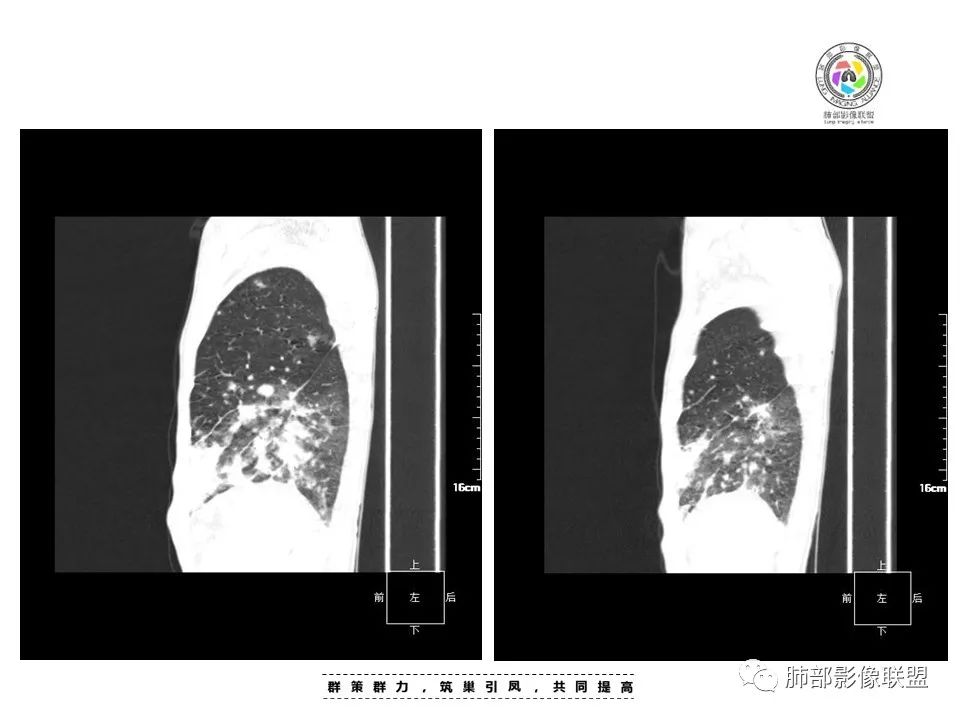

周一晚读病例:男性45岁,发热、纳差,全身散在暗紫色皮疹,结合CD4,符合HIV;肺部影像表现:两肺散在实性结节及磨玻璃密度影,实性结节伴晕征,部分沿支气管血管束分布,支气管血管束增粗,以两肺下叶为著,类似火焰征,双侧胸腔少量积液;首先考虑卡波西肉瘤,鉴别淋巴瘤增值性病变,淋巴瘤样肉芽肿/淋巴瘤,最后挂上马尔尼菲青霉菌病。

中年男性,发热、全身散在暗紫色丘疹,查CD4+T细胞64个/ul,临床信息提示AIDS并发卡波西肉瘤;CT提示双肺多发实性结节影及毛玻璃结节,部分呈点晕征,右上肺大姐姐边缘膨隆、分叶伴晕;双下肺结节沿支气管血管束分布,中轴间质增粗,部分支气管堵塞,叶间裂结节状增厚,部分结节胸膜下分布,可疑局部小叶间隔增厚,肺部病变呈淋巴分布特点,结合临床肺部病变考虑肺卡波西肉瘤,鉴别淋巴瘤。

两肺弥漫性性结节状、小片状及片状带晕的病灶,煎蛋征、点晕征,主要分布两肺中下叶,病灶周围小叶间隔增厚呈网格状影,部分病灶累及胸膜,伴两侧胸膜增厚。

2.本例双肺小叶间隔增厚明显,多发结节影及片状实性密度影,沿血管支气管束分布为主,两侧较为对称,病灶多环以磨玻璃晕,边界不清。

双侧胸腔少量积液。双肺门及纵隔未见明确肿大淋巴结,纵隔结构间隙模糊。

3.有学者将这种具有沿双肺支气管束分布的实性密度片影描述为“火焰征”,认为具有一定特征性,单就影像表现而言,这种影像表现也可以见于其他病损或多种病理改变的叠加。

1.结节型:两肺沿支气管血管束分布的结节影,呈火焰状或星芒状、挂果征,局部周围出血磨玻璃影(肺泡出血或水肿)。

2.支气管血管束增粗型:

肺门周围支气管壁呈“套袖样”改变。

3.肺炎渗出型:

斑片渗出影,部分融合呈“火焰样”,同时有火焰样结节,小叶间隔增厚等表现。

还可以有纵隔及腋下淋巴结增大,胸腔积液等表现。